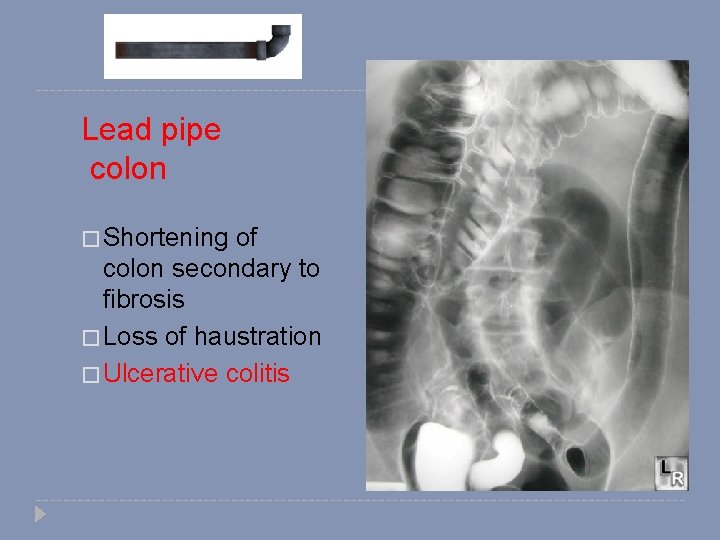

Lead pipe colon � Shortening of colon secondary to fibrosis � Loss of haustration � Ulcerative colitis